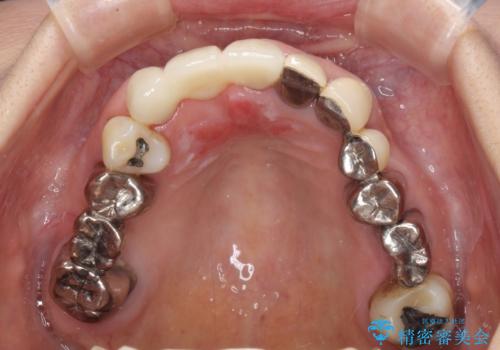

仮歯に置き換えた時点で見た目が大きく改善され、人目を気にすることがなくなりました。

オールセラミッククラウンは、仮歯以上に快適な舌触りや、本物の歯のような外観となり、患者様には大変満足していただけました。